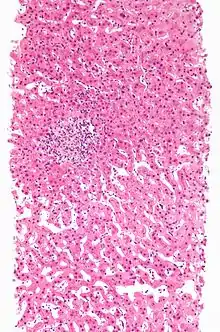

![]() | |

| A rash due to a drug reaction |